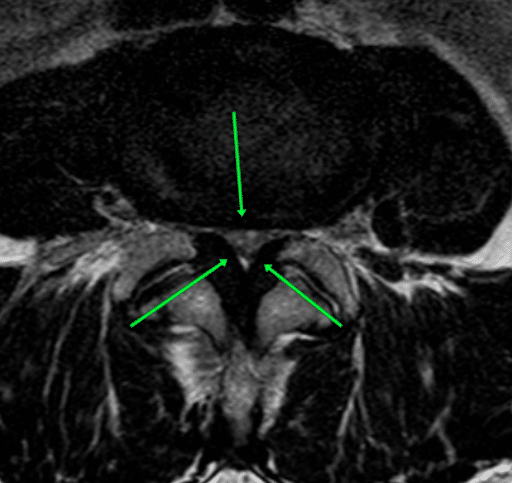

Przed operacją zwężenie kanału może być widoczne na obrazach diagnostycznych, takich jak rezonans magnetyczny. Przerośnięte więzadła oraz uwypuklenia krążków międzykręgowych ograniczają przestrzeń dla struktur nerwowych, powodując ból oraz zaburzenia neurologiczne.

Brak widocznej przestrzeni (średnicy) kanału kręgowego. Strzałki wskazują przerost więzadła żółtego oraz uwypuklenie krążka międzykręgowego, które powodują zwężenie kanału. Zwężenie takie powoduje istotny ucisk na korzenie nerwów i ból.